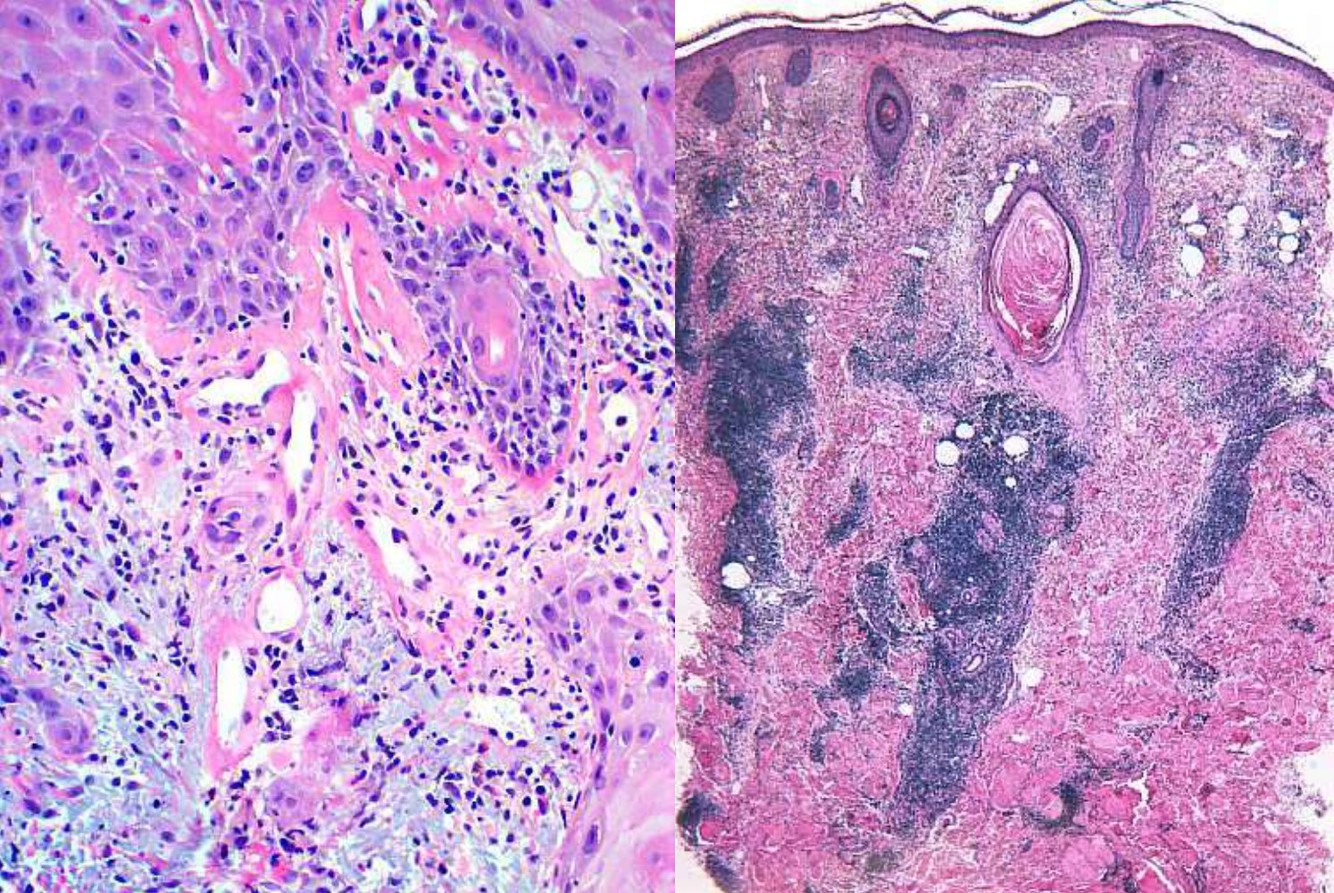

Dermatofibroma with aneurysmal change

DDx

Vascular tumor